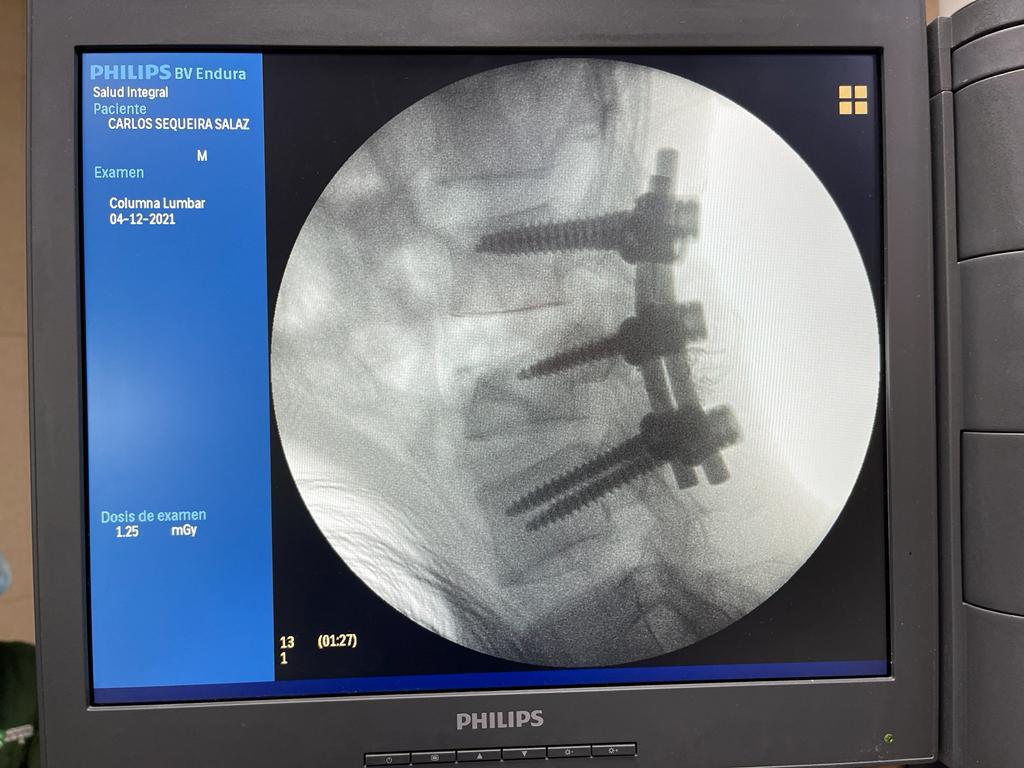

4. Fusión Vertebral (Lumbosacra o Cervical)

¿Qué es?

Cirugía que une dos o más vértebras para estabilizar la columna y aliviar el dolor.

Fusión Vertebral (Cervical o Lumbosacra)

Es un procedimiento quirúrgico que busca estabilizar la columna vertebral uniendo de forma permanente dos o más vértebras. Se utilizan tornillos, barras y, en ocasiones, una caja intersomática con injerto óseo, para que las vértebras se fusionen en una sola unidad sólida.